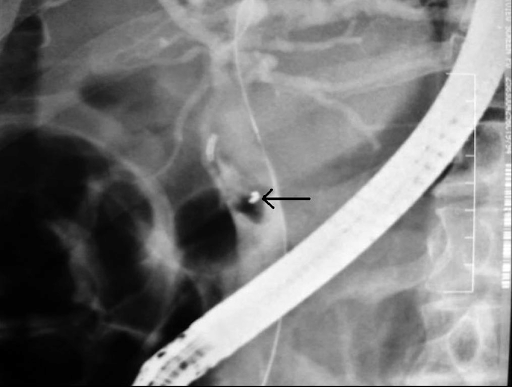

Sỏi ống mật chủ gây đau, khó chịu và ảnh hưởng đến sức khỏe, sinh hoạt và công việc của người bệnh. Để điều trị sỏi ống mật chủ, có nhiều phương pháp khác nhau được sử dụng. Tuy nhiên, để đạt hiệu quả cao và đảm bảo an toàn cho bệnh nhân, các phương pháp này cần được áp dụng đúng cách và theo sự hướng dẫn của các chuyên gia y tế. Trong bài viết này, chúng ta sẽ tìm hiểu về những phương pháp điều trị sỏi ống mật chủ phổ biến hiện nay.